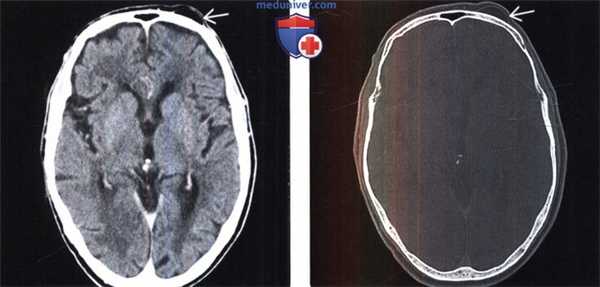

(Слева) Бесконтрастная КТ, аксиальный срез: у мужчины 81 года, доставленного в приемное отделение с измененным психическим статусом определяется выраженно гиподенсное поражение волосистой части кожи головы над лобной костью слева.

(Справа) КТ, костное окно: у этого же пациента отмечается, что поражение имеет ту же плотность, что и подкожная жировая клетчатка. Липомы волосистой части кожи головы как случайные находки наблюдаются нередко. Обычно считается, что внутричерепные липомы — мальформативные, а не опухолевые образования.